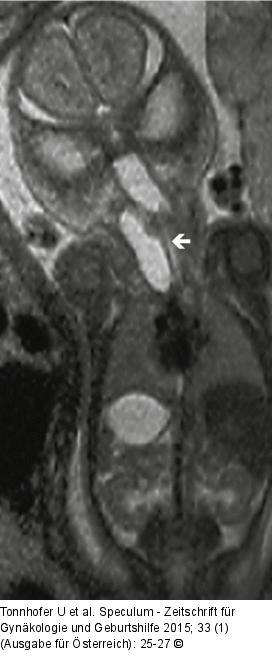

Abbildung 3: Pränataldiagnostik-Therapie Fetales MRT branchiogene Zyste. |

Fetales MRT branchiogene Zyste. |